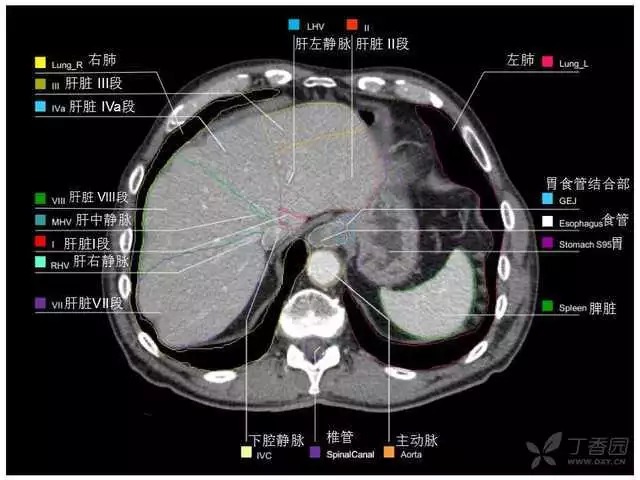

腹部肝脏高清CT断层的图谱

全腹部高清CT图谱,淋巴结彩色图谱,血管解剖图谱大汇总!

超声肝脏分叶及分段

肝脏分段和基本解剖学标志